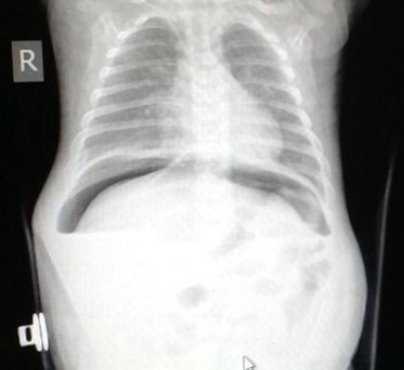

Рис. 1. Подкапсульная гематома печени

Рентгенологически при разрывах полого органа — свободный газ, при разрывах паренхиматозных органов — свободная жидкость в нижних отделах брюшной полости, при тупой травме — вздутие петель кишечника, нечеткость контуров их и, иногда, неравномерное распределение, как петель, так и его содержимого.

Рис.2 Травма живота: разрыв полого органа